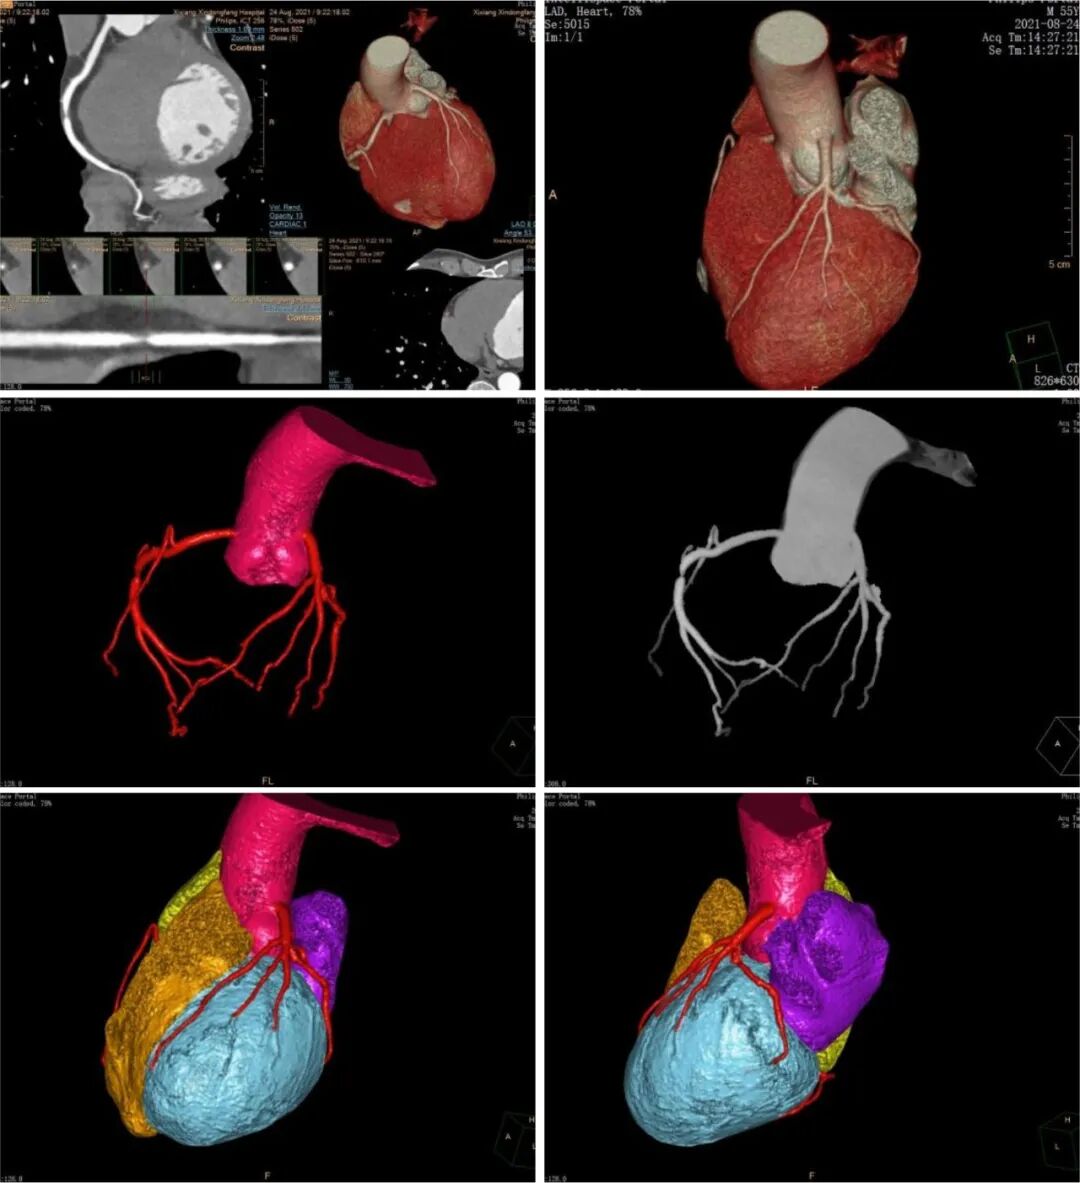

我院飞利浦128排256层光谱CT具有扫描速度快、图像清晰度高、辐射计量低、信息量大等特点。超宽的128排探测器,每圈扫描采集256层图像,对于全身及局部CT造影检查特别是心胸肺部等超高分辨扫描具有显著优势,其X线辐射比常规CT正常的辐射量大幅度减少;超高空间分辨率,可以显示1cm以下的微小病变,可进行大范围动态多器官的影像检查。

临床应用领域也十分广泛,可以完成CT心脏冠脉CTA(血管造影)检查、肺动脉CTA成像检查、周围血管CTA成像检查、骨关节CT三维重建、呼吸系统、消化系统以及人体各个部位疾病的成像检查,还可以通过高低能量扫描对痛风结节的分析。